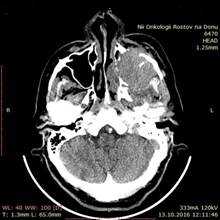

Больной В., 1947 года рождения, поступил в отделение опухолей головы и шеи ФГБУ «РНИОИ» МЗ РФ 17.10.2016 г. с жалобами на опухоль в области левой щеки. При осмотре - лимфатические узлы шеи не увеличены, носовое дыхание не затруднено, лицо асимметрично за счет распространяющейся в мягкие ткани левой щеки опухоли левой верхнечелюстной пазухи. При пальпации деструкция нижнеорбитального края не определяется. При передней риноскопии опухоль не определяется. Остальные ЛОР-органы без видимой онкопатологии. СРКТ от 13.10.2016 г.: «Слева опухоль верхнечелюстной пазухи 5,6х5 см с неоднородной структурой, прорастанием ее передней стенки с распространением мягкотканого компонента опухоли на мягкие ткани лица, участок деструкции альвеолярного края верхней челюсти слева» (рис. 2).

Рис. 2. СРКТ придаточных пазух носа: слева опухоль верхнечелюстной пазухи 5,6х5 см с неоднородной структурой, прорастанием ее передней стенки с распространением мягкотканого компонента опухоли на мягкие ткани лица, участок деструкции альвеолярного края верхней челюсти слева